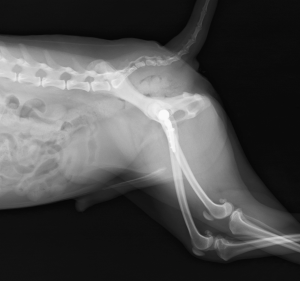

術後レントゲン画像

大腿骨が扁平な形をしていたため、予定していたインプラント(ステム)の厚みが合わず、大腿骨の髄腔内を削るなどの試行錯誤をしました。最終的に、体重強度の許容範囲内で1サイズ小さいインプラントを使用しました。

2週間のケージレスト、並びにレーザー療法を行いました。術後1週間ほどで痛みや違和感が治まってきたのか、徐々に患肢への負重がしっかりしてきました。ケージ内での動きには大きな問題は感じられず、退院時の歩様も良好でした。脱臼症例ということもあり、筋肉量に左右差がなかったことが歩様の安定に繋がったと考えられます。

術後1ヶ月半、術後3ヶ月の検診でも、足の様子は良好で、大腿分の筋肉量に左右差はありませんでした。